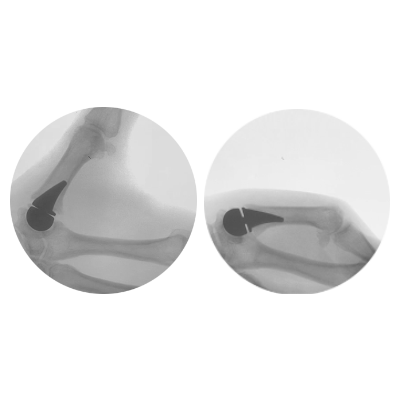

Arthroplasty of the thumb is much like a total knee or hip replacement. All or part of the thumb joint is removed and replaced with a prosthesis.